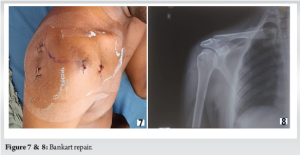

Bankart repair

The anteroinferior labrum was reattached using suture anchors placed at 3, 4, and 5 o’clock positions on the glenoid rim (Fig.7, 8).